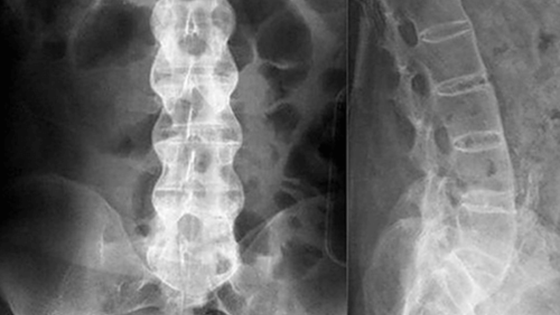

В России разработали новый эффективный препарат против болезни Бехтерева. В беседе с  РИА Новости академик Сергей Лукьянов напомнил, что при этой болезни у человека происходит окостенение позвоночника и различных суставов. Из-за этого больной теряет подвижность, постоянно испытывает боль.

Российским ученым удалось разработать препарат, который снимает болевой синдром и скованность, уточнил Лукьянов. Лекарство уже прошло третье клиническое испытание и показало свою эффективность.